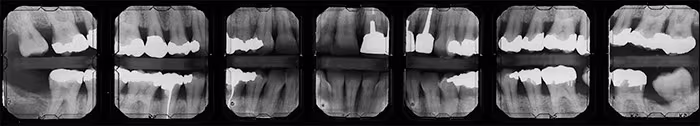

Bitewing Surveys

There are several landmarks recorded on molar bitewing radiographs whether horizontal (Figure 32) or vertical (Figure 33) in orientation. The most common structures observed are the external oblique ridge and maxillary tuberosity.

Figure 32: Horizontal Bitewing Survey

Figure 33: Vertical Bitewing Survey